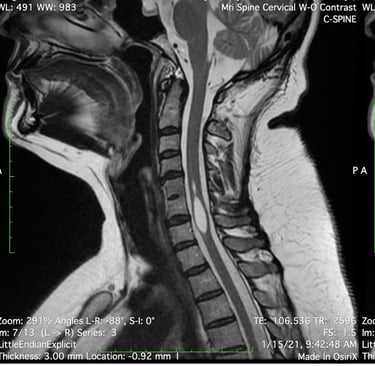

Is a neurological disorder in which a fluid-filled cyst (syrinx) forms within the spinal cord. The syrinx can get big enough to damage the spinal cord and compress and injure the nerve fibers that carry information to and from the brain to the body. Some studies have found the prevalence of syringomyelia to be 8.4 cases in 100,000 in the U.S.

In syringomyelia, the watery liquid known as cerebrospinal fluid (CSF)—which surrounds and protects the brain and spinal cord—builds up within the tissue of the spinal cord, expands the central canal, and then forms a syrinx. Generally, a syrinx develops when the normal flow of CSF around the spinal cord or lower brain stem is disturbed. When syrinxes affect the brain stem, the condition is called syringobulbia.

MRI Image of the cyst